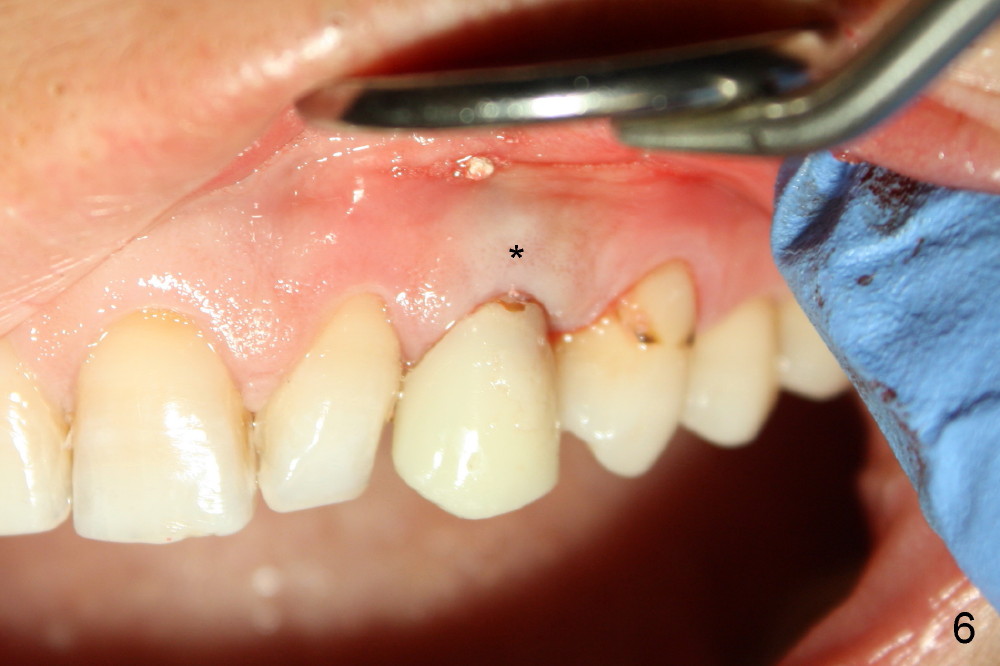

The 42-year-old lady refuses to take antibiotic prior to surgery due to lactation. The extraction of the upper left deciduous canine is not difficult as expected. There appears to be no granulation tissue. What is unexpected is difficulty in osteotomy. Initial osteotomy is too palatal, apparently perforating the palatal plate. The osteotomy has to be changed: slightly palatal to the center of the original socket (Fig.1: 2 mm pilot drill). As drills increase in diameter, the coronal end of the drills have to be tilted buccally, because it feels like that the labial plate at the apical end is going to be perforated. When 4.5x14 mm bone level implant is placed, the implant is sticking out too much (Fig.2). To alleviate this cosmetic issue, the implant is placed deeper (Fig.3). A 25º angled abutment is placed with heavy labial reduction (Fig.4,5). The patient is pleased with a stable new tooth, but the operator is not (Fig.6). Removal of the implant may be not the wildest guess. Two or three days postop, the patient reports pain and swelling. The symptoms disappears after antibiotic. One week follow up reveals wound healing normal. The gingiva returns to its normal color, as compared to purplish appearance in Fig.4,6 (immediately postop). In fact, the implant fails in a month.